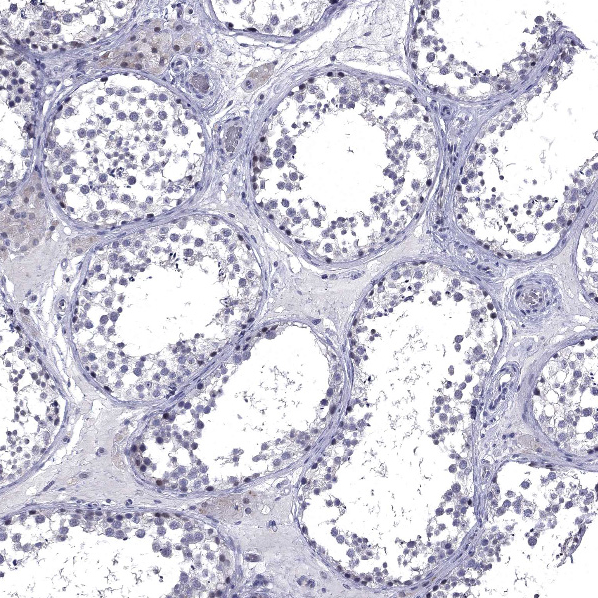

Immunohistochemistry analysis in human small intestine and liver tissues using HPA040591 antibody. Corresponding HTR4 RNA-seq data are presented for the same tissues.